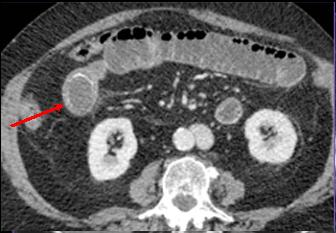

Image TDM en coupe axiale :

Signe de feces' c'est la retention de fesce dans la

portion sus -lesionelle de l'intestin ( fleche

blanche ) . |